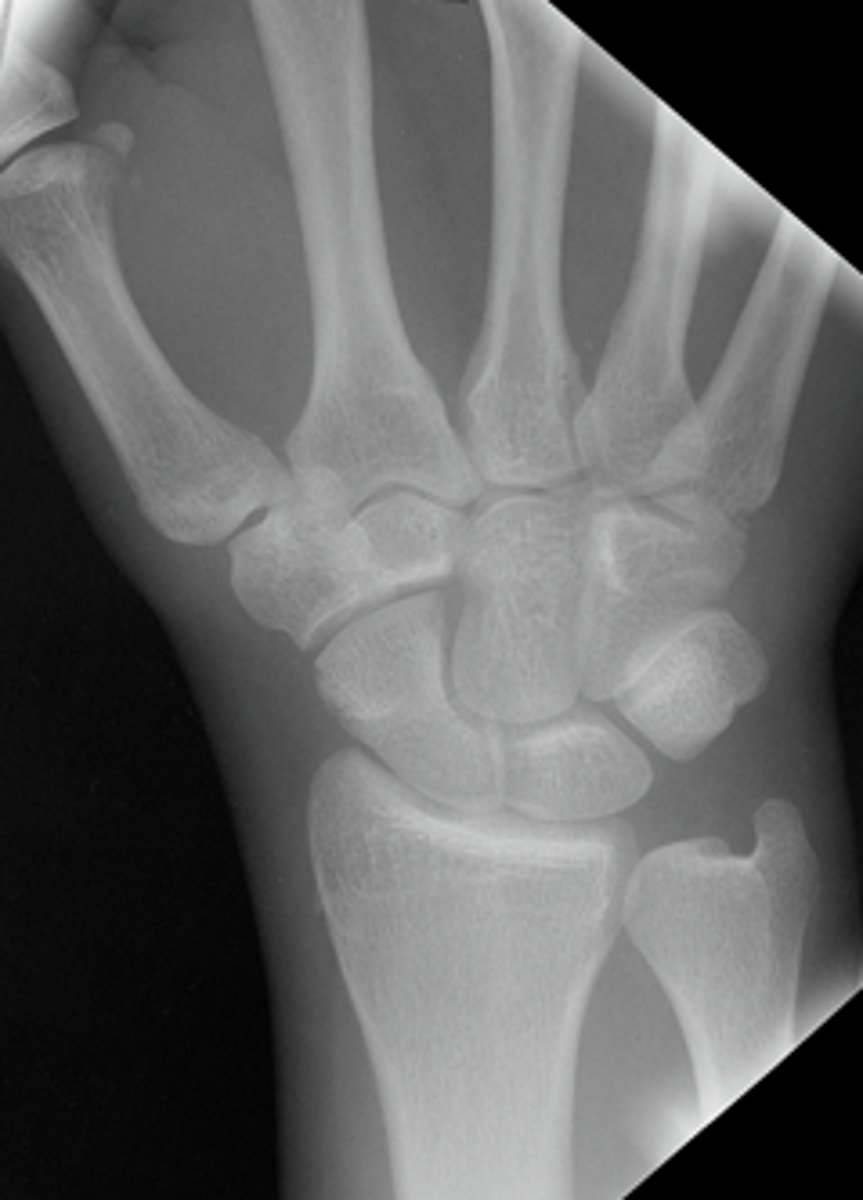

Patient presents to the ER following a fall complaining of pain in the "snuff box". Do you see any thing?

Answer

Possible AVN. Its sclerotic looking

The films were normal now what do you want to do? What other imaging could you also consider?

-Follow up in another 7-10 days with x-ray

-Could also use MRI

Here it is 3 months later

Proximal mid and distal poles are sclerotic